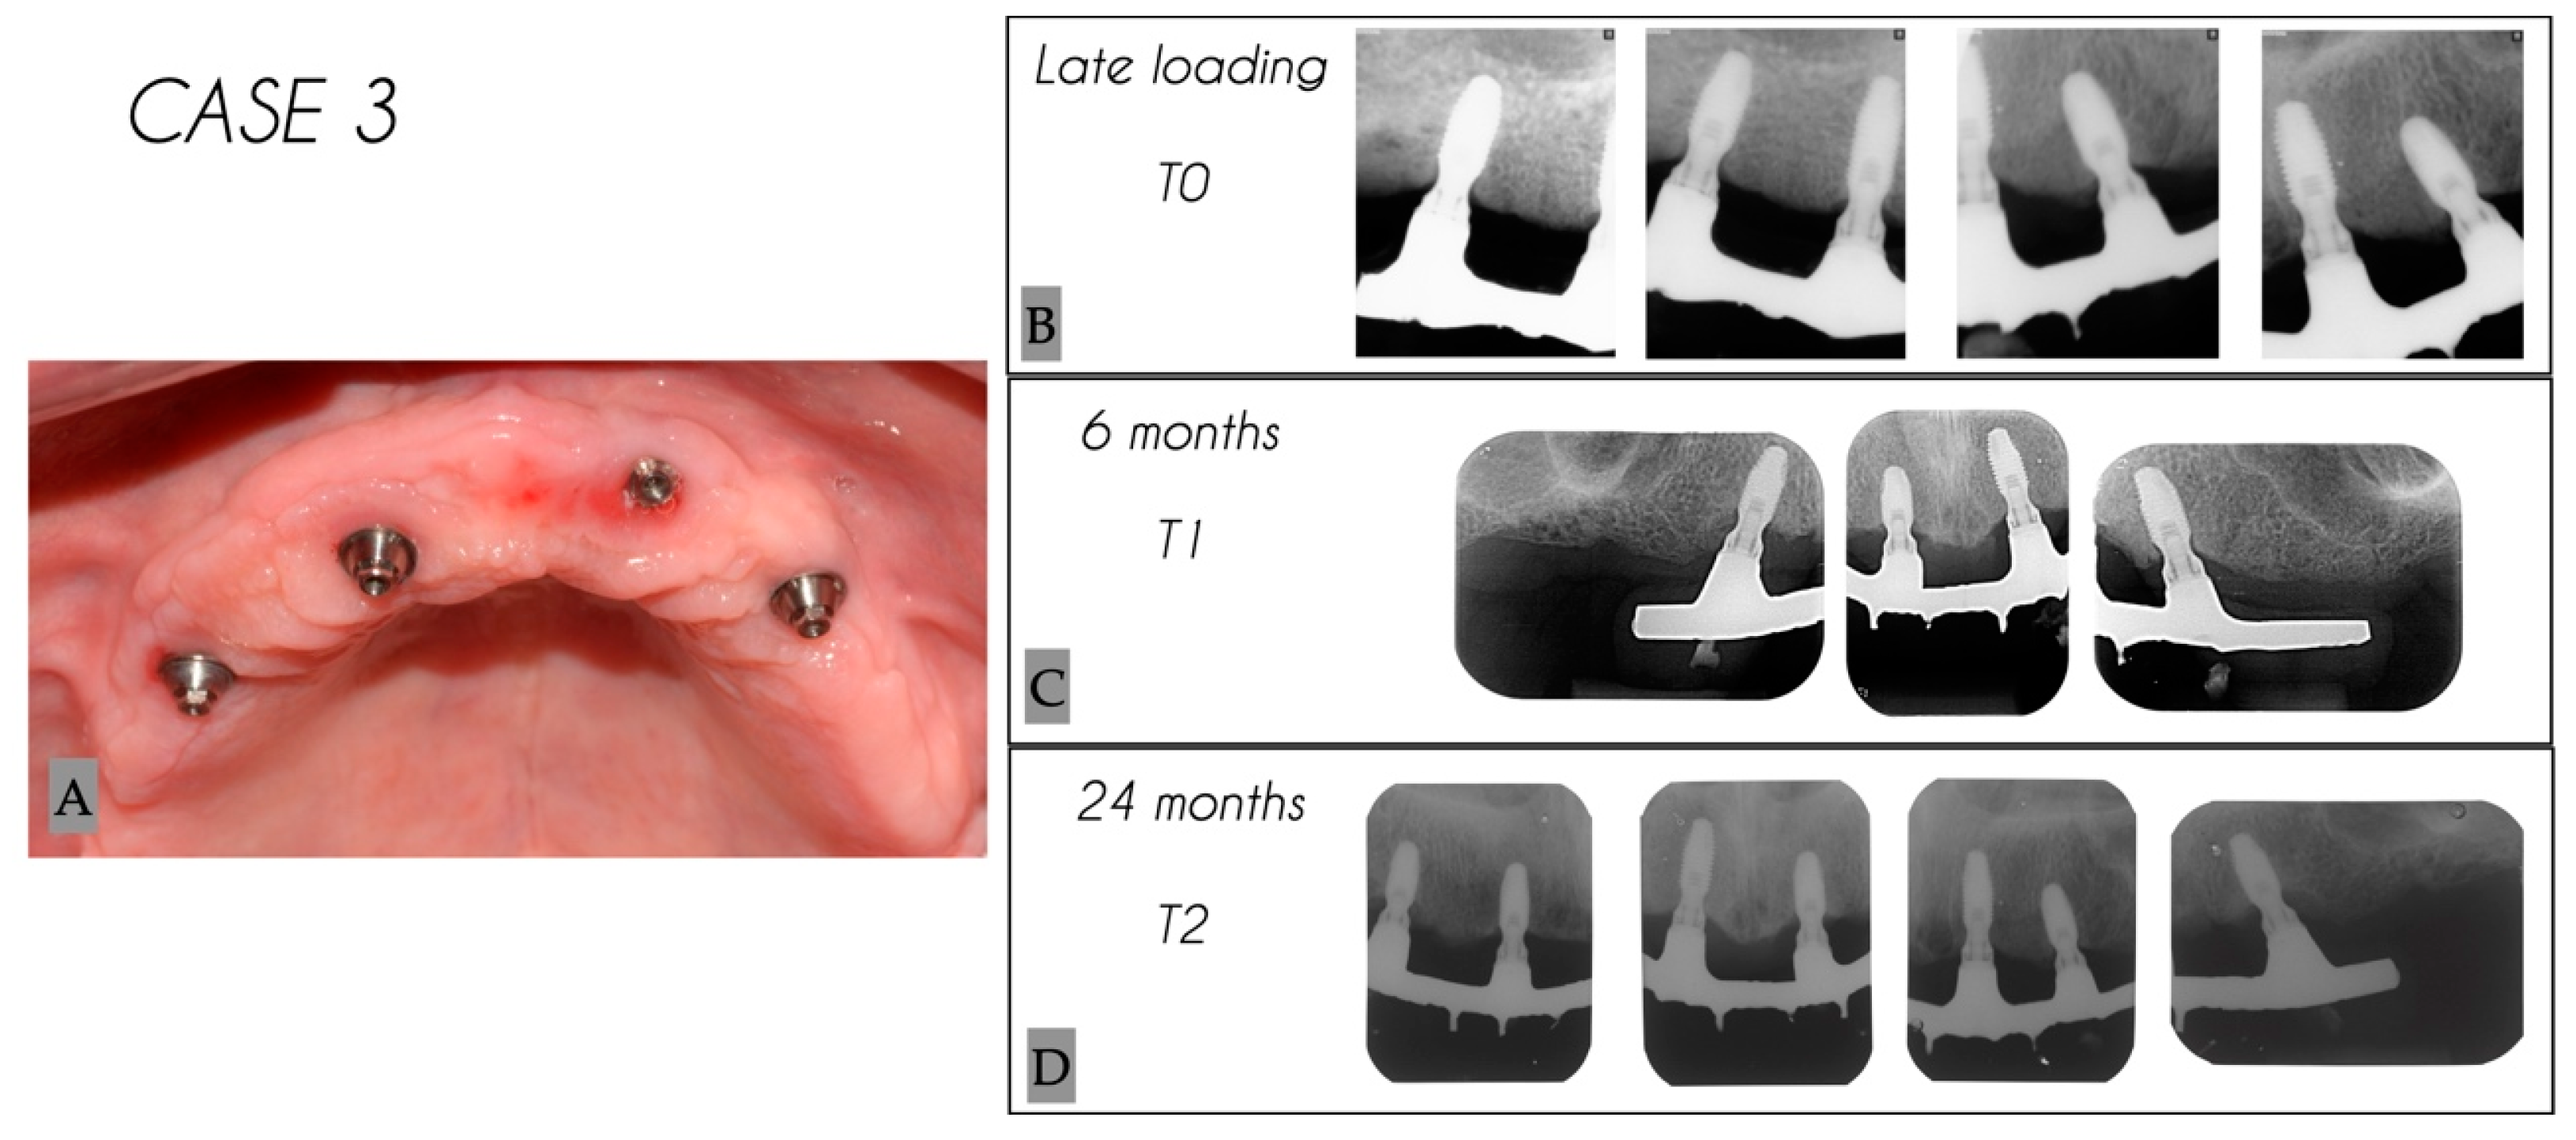

| Case No. | Tooth No. | Initial MBL (mm) | MBL 6 Months (mm) | MBL 24 Months (mm) | KM 6 Months (mm) | KM 24 Months (mm) |

|---|---|---|---|---|---|---|

| 3 | 24 | 1.43 | 1.51 | 1.82 | 6 | 6 |

| 3 | 22 | 0.38 | 0.6 | 0.97 | 3 | 3 |

| 3 | 12 | 1.57 | 1.86 | 2.23 | 3 | 3 |

| 3 | 15 | 1.81 | 1.89 | 1.99 | 4 | 4 |

| Mean | 1.30 | 1.47 | 1.75 | 4.0 | 4.0 | |